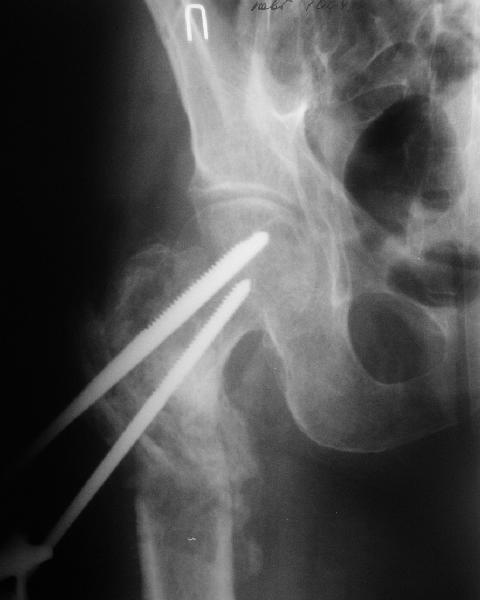

В приложении пример пациента, близкого по картине к тому, что представил Виктор (варус и смещение периферического отломка на поперечник кзади). Сделали как раз то, что Виктор исходно намеревался - аппаратная коррекция и затем гамма.

По опыту подобных случаев, аппарат лучше на бедро, без таза пока. В проксимальный фрагмент 3 стержня по оси шейки. Дистальный - хватит 1 стержня или 2 спиц в дистальном метафизе и 1 стержня вверху. Если планируете гвоздь, надо с гиперкоррекцией восстановить длину и ось, т.е. вальгизировать проксимальный отдел. При наложении аппарата сделать остеоклазию, добиться уверенной подвижности. Регенерат не нужен, тяните на пределе переносимости пациентом - хоть 2 см/сут. Обычно меньше.

Второй этап - на следующий день после окончания коррекции.

Если все получилось, т.е. закрыто сопоставить с гиперкоррекцией, накладываете дистрактор таз-бедро или используете тракционный стол, и гвоздь можно делать закрыто. Пластика то есть не нужна. Если клинковая пластина - может получиться как при меежвертельной остеотомии, боковая компрессия by mismatch. Тогда тоже пластика не нужна. Если не получатся, можно и сделать.

Одномоментно сделать можно, но это может быть травматичнее, и лучше дистрактор какой-то все равно. Если будет оставаться варус, с ним лучше

справиться можно с помощью пластины, не гвоздя.